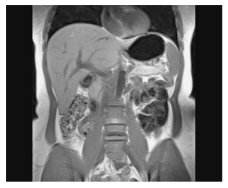

Assinale a alternativa que apresenta a estrutura que NÃO pode ser visualizada na imagem a seguir.

A

Estômago.

B

Músculo oblíquo interno.

C

Músculo trapézio.

D

Aorta abdominal.

E

Músculo psoas maior.